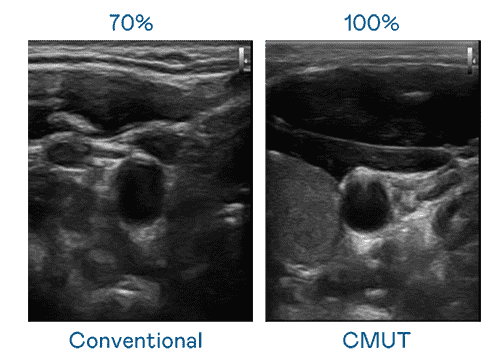

CMUT 技术是一种用电容式微机电元件来产生超音波讯号的技术。。与传统 PZT 压电式技术相比,,,CMUT 频宽增加 30%,,,,更宽频的超音波讯号让影像解析度大幅提升,,,,是实现高影像品质医疗超音波扫描、、、、促进精准医疗发展的关键技术。。。。

大频宽带来超清晰影像

超音波影像的解析度高低,,,,首先取决于探头能发出的讯号频宽。。尊龙z6 CMUT 可提供高清晰的超音波讯号,,,,提供高频宽、、、高灵敏度、、、影像纹理细节更高的超音波影像,,,,协助医护人员缩短影像判读时间及利用精准的医疗影像进行诊断。。。